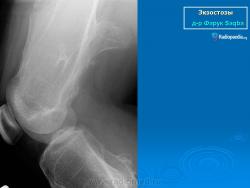

Локализация остеохондромы: частота поражения отдельных костей различна; нижний коней бедренной кости, верхние отделы плечевой и большеберцовой костей поражаются более чем у половины больных. На всем протяжении остеохондрома покрыта надкостницей. Она может быть обнаружена и в других костях, за исключением костей лицевого черепа. Все же поражение костей позвоночника, кистей рук и стоп встречается редко. При рентгенологическом исследовании видна типичная картина узкого или широкого выроста вблизи эпифизарной части пораженной кости. Обычно плотность узла неоднородная, имеются многочисленные плотные участки, соответствующие обызвествленным хрящевым долькам. Хрящевая «шапочка» большей частью не определяется, поскольку хрящ остается необызвествленным. Она может быть выявлена только при магнитно-резонансной томографии.